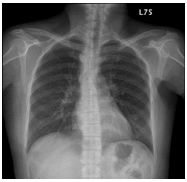

10. CC: 咳嗽 1 周,有痰